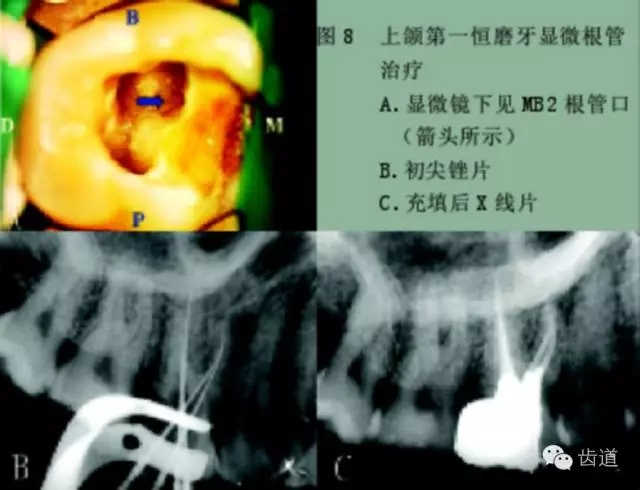

手術(shù)顯微鏡是用于尋找隱藏或遺漏的根管最重要的工具。因為手術(shù)顯微鏡能夠幫助醫(yī)生觀察到肉眼或普通放大鏡無法分辨的根管口和微小病損。在手術(shù)顯微鏡下,利用高倍數(shù)(16~24倍)的放大作用以及理想的照明條件,仔細(xì)檢查患牙的髓室底,許多細(xì)微的解剖結(jié)構(gòu)能容易被發(fā)現(xiàn)。

為了光線能充分進(jìn)入髓腔,髓室頂應(yīng)完全揭去,開髓口的形態(tài)應(yīng)根據(jù)具體牙位進(jìn)行適當(dāng)修改,使得所有根管口都能夠充分暴露。同時,對髓底進(jìn)行美藍(lán)染色也有助于根管口和微小病損的識別。

對于有些牙根管在根管口下3~5毫米處分叉以及近頰和遠(yuǎn)頰根管口非常接近的上頜第二磨牙,手術(shù)顯微鏡更是相當(dāng)有價值的工具。因為根管的分叉點和獨立的根管口能清楚地在顯微鏡下被觀察到。